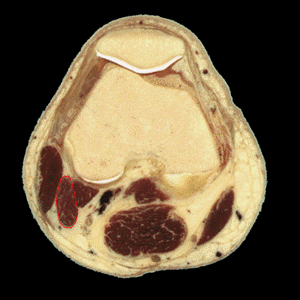

MUSCULO GEMELO

Definici�n: los m�sculos gemelos, formados por las cabezas medial y lateral se extienden en la parte syperficial del compartimento posterior de la pantorilla

Origen: Las cabezas medial y latreral del m�sculo gemelo salen de los c�ndilos medial y lateral del f�mur, respectivamente. Las dos cabezas se unen en la parte superior de la pantorilla.

Inserci�n: El m�sculo forma un tend�n ancho y plano a nivel de la pantorrilla media. El tend�n soleo se insera en la parte anterior del tend�n del gemelo para formar el tend�n de Aquiles que, a su vez, se inserta en la parte posterior del calc�neo posterior

Inervaci�n: El m�sculo gemelo est� inervado por el nervio tibial (S1, S2). El aporte sangu�neo est� asegurado por la arterial posterior tibial artery.

Funci�n: El m�sculo gemelo flexiona la pierna, extiende el pie (flexi�n plantar) y es supinador y abductor del mismo.